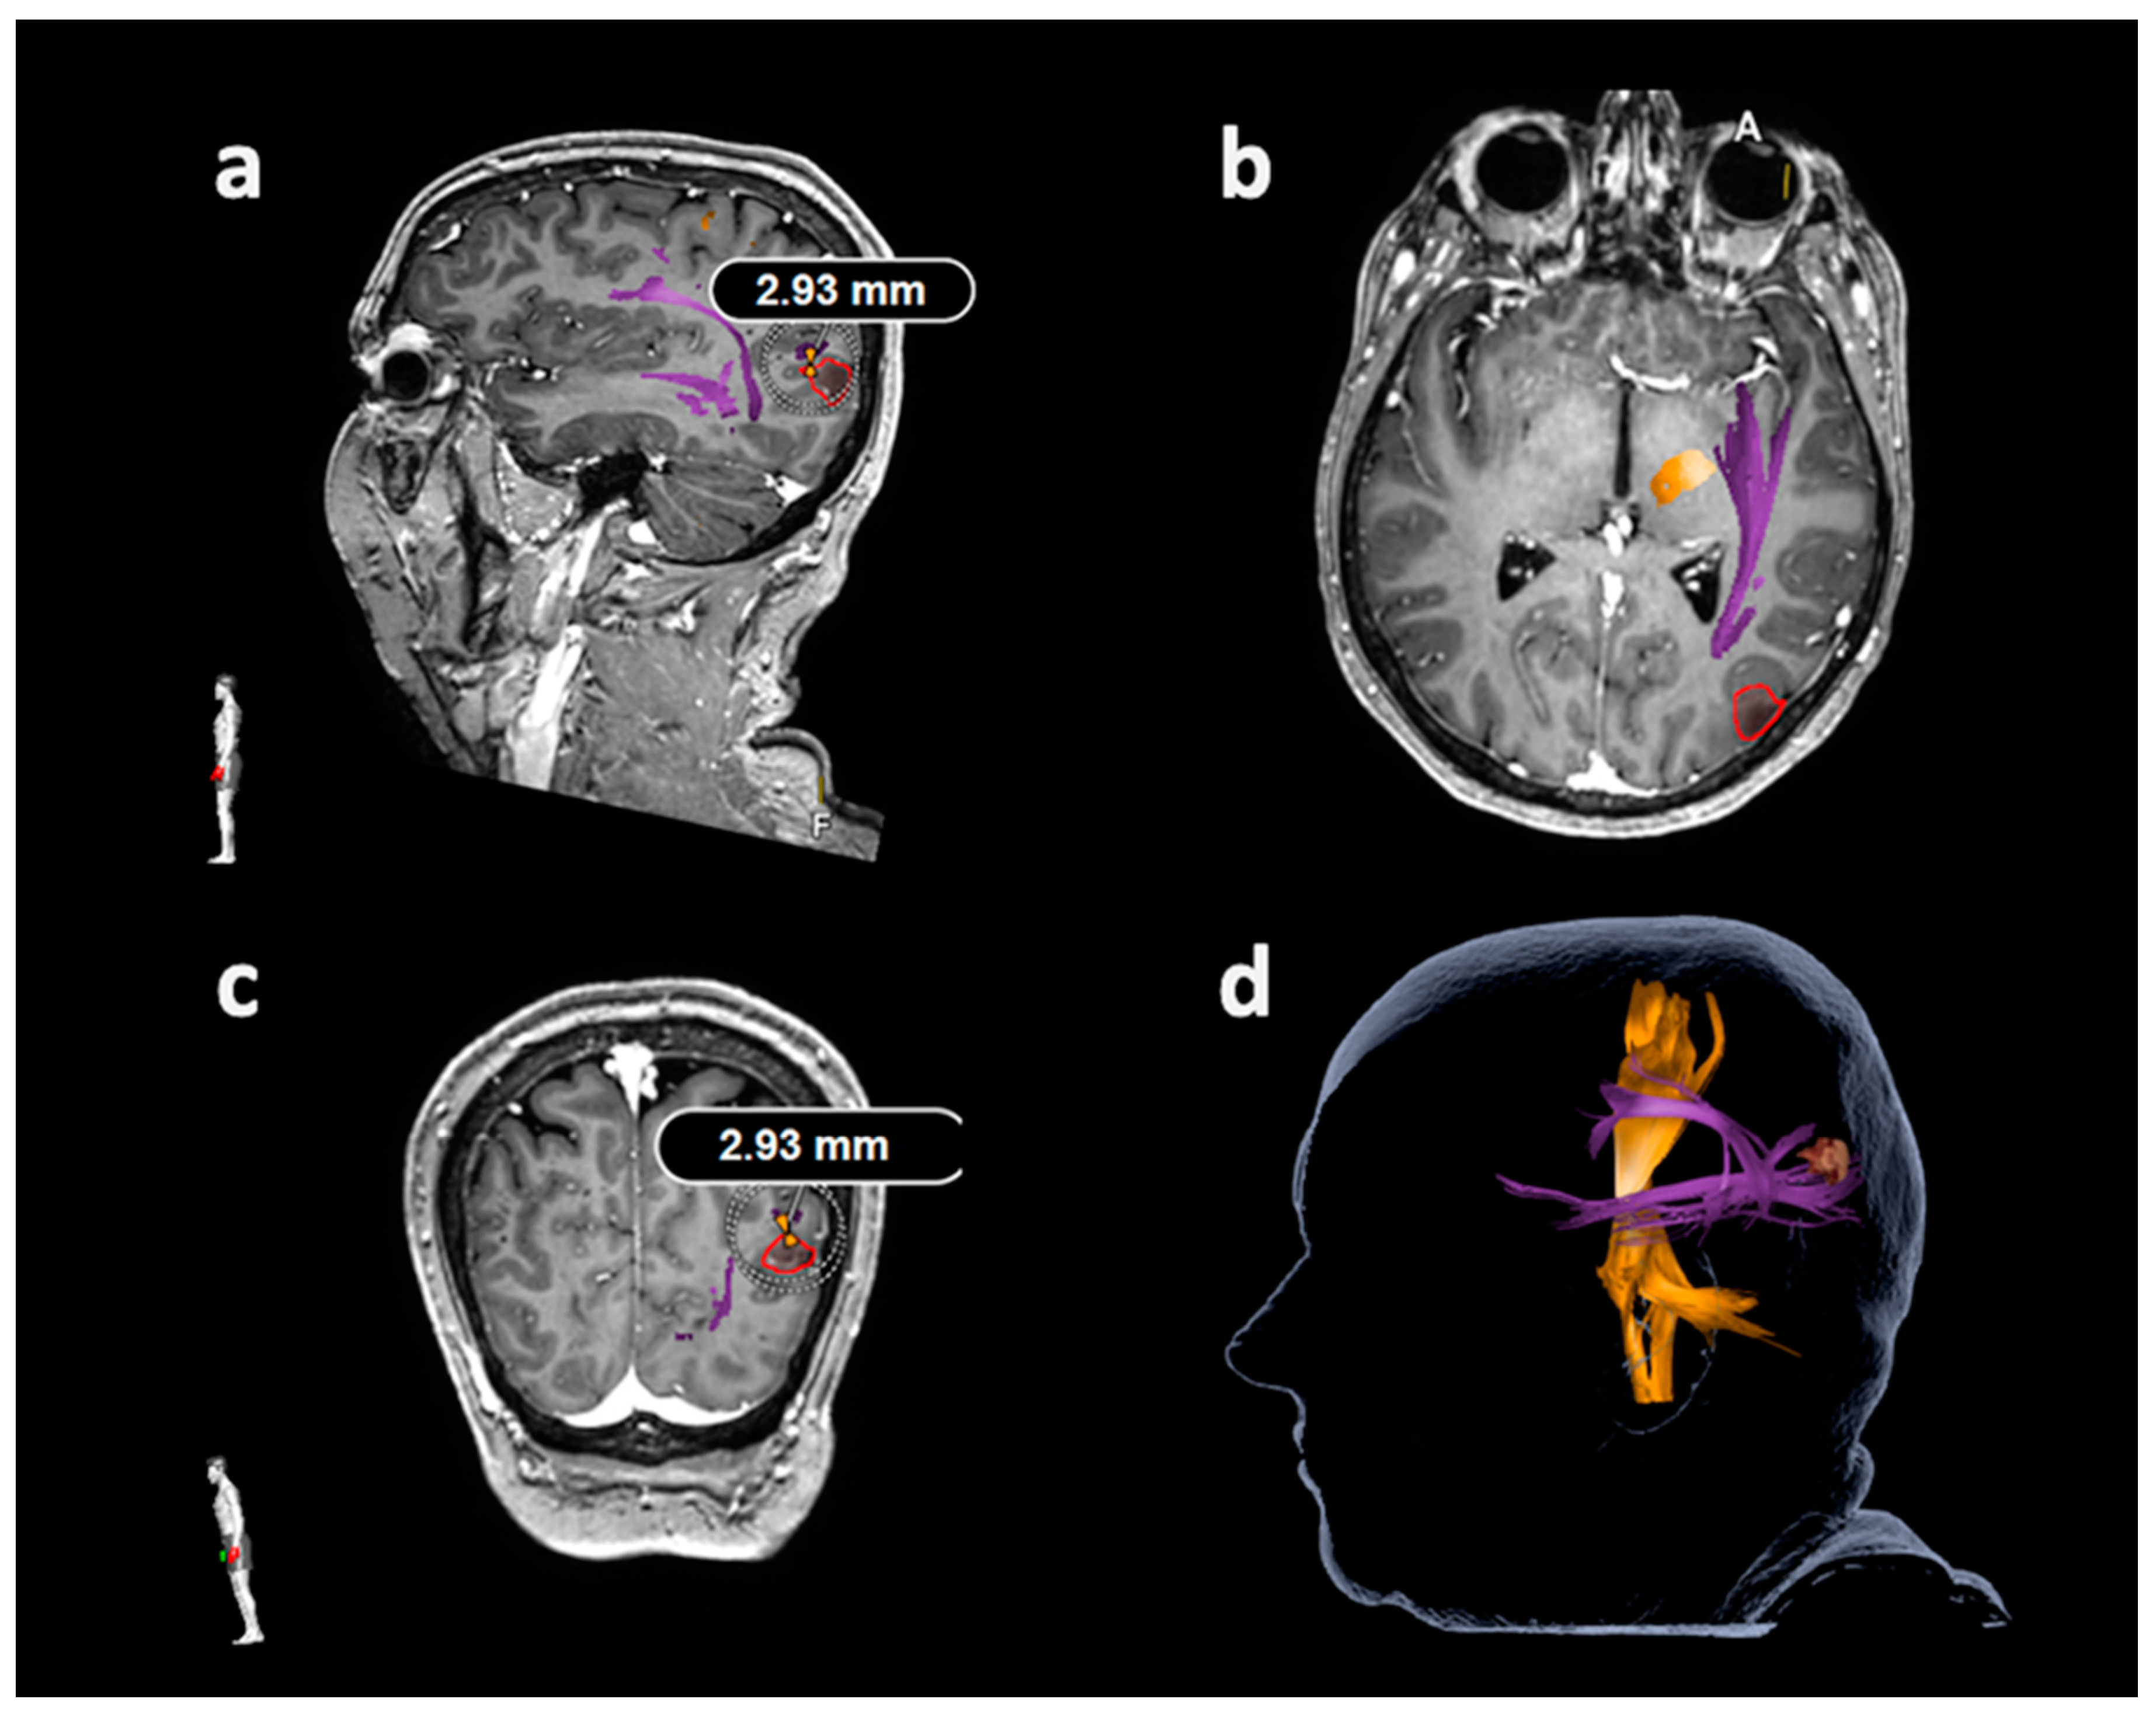

Figure 4. Measurement of the lesion-to-tract distance (LTD) in relation to the frontooccipital fascicle (FoF). This illustrative patient case illustrates the LTD measurement in relation to the FoF as the closest language-related tract except for the arcuate fascicle (AF), applying diffusion tensor imaging fiber tracking (DTI FT) based on the language map derived from navigated transcranial magnetic stimulation (nTMS). The FoF and AF are depicted in purple, the corticospinal tract is shown in orange, and the tumor volume is enclosed in red. During LTD measurements, all planes were considered ((a): sagittal plane, (b): axial plane, (c): coronal plane), with the LTD measurement of 2.93 mm being shown in parts (a) and (c) in this patient case. The three-dimensional (3D) head model including the structures of interest is provided in part (d).

Tractography of the AF or other closest language-related tracts considering the superior longitudinal fascicle (SLF), inferior longitudinal fascicle (ILF), uncinate fascicle (UC), and frontooccipital fascicle (FoF) was performed with language-positive nTMS points with a rim of 5 mm as the only ROI (Figure 2 and Figure 3) [23,27,30]. Similar to nTMS-based DTI FT of the CST, a minimum FL of 100 mm was combined with 25%, 50%, and 75% FAT [23,27,30]. The LTD for the AF or other closest language-related tract (either SLF, ILF, UC, or FoF) was defined in FLAIR and/or contrast-enhanced 3D gradient echo sequences by linearly measuring the minimum distance between the border of the solid tumor mass and the closest fibers of the AF or other closest language-related tracts (Figure 4) [27].